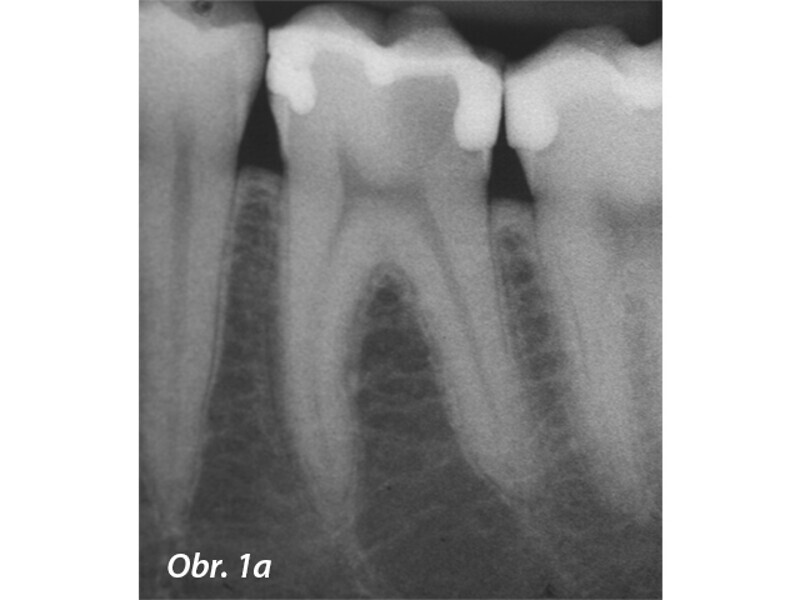

Aplikace MTA s použitím Produit Dentaires (PD) MAP System